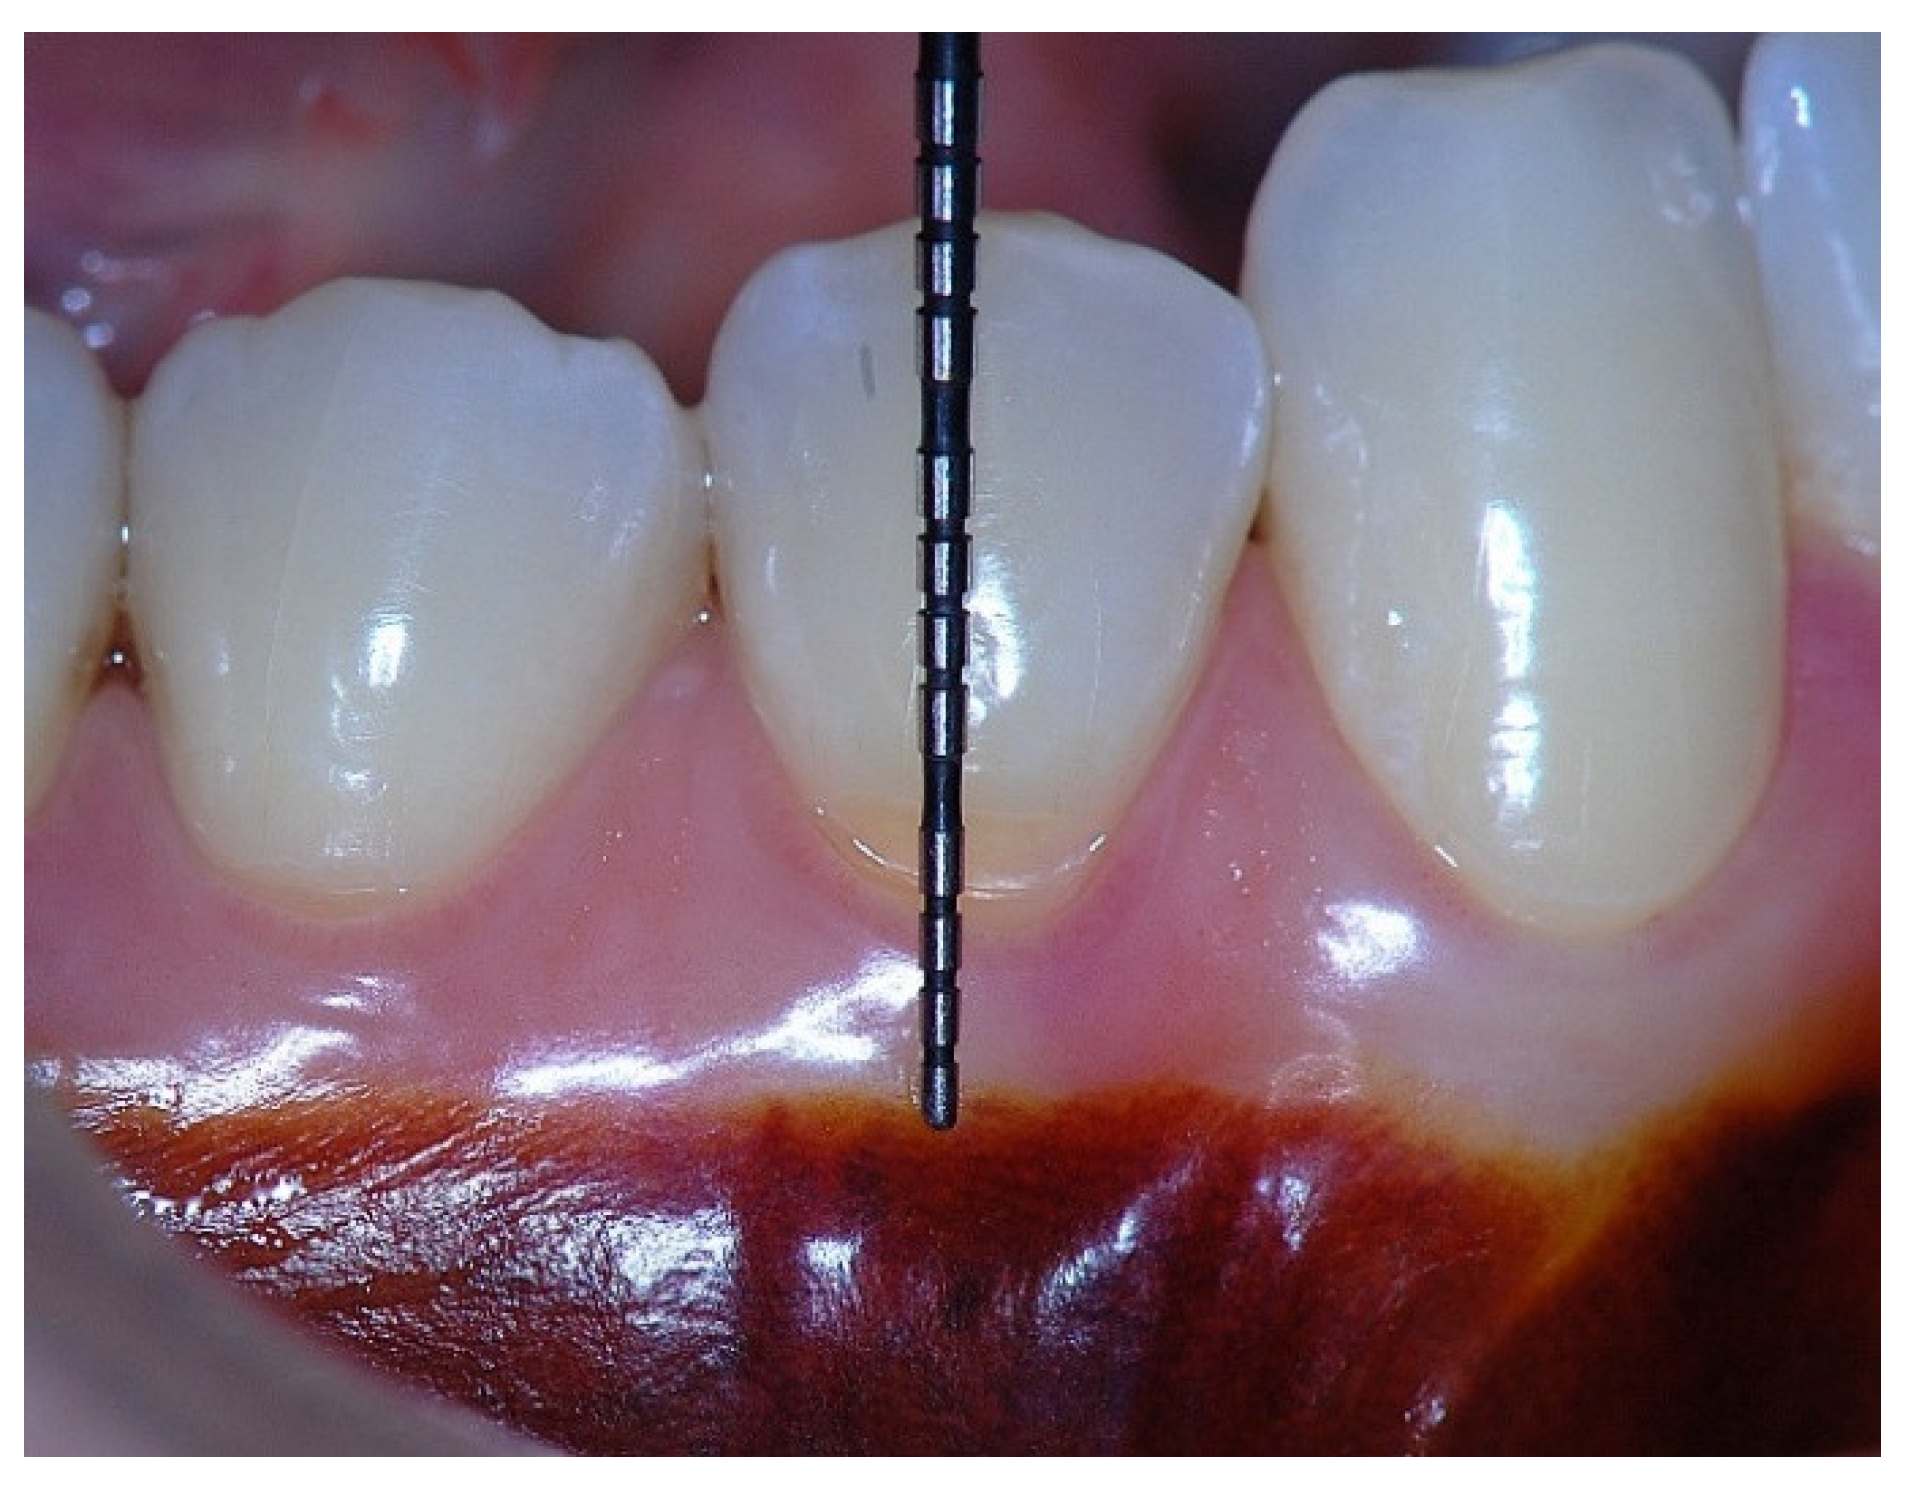

Figure 1. Probing depth of 1mm and 1mm of the epithelial attachment.

In a clinical scenario with 2 mm of keratinized tissue (KT) and a sulcus depth of 1 mm, a stable, firm, and resistant connective attachment is not present [1]. This occurs because most of the connective tissue fibers inserting onto the root surface are associated with non-keratinized, mobile mucosal tissues (Figure 1), which are elastic in nature and therefore unable to stabilize the gingival margin (Figure 4 and Figure 5). Conversely, when these fibers are embedded within keratinized tissue, they are firmly attached to the tooth and bone and are comparatively immobile, thereby contributing to gingival margin stability (Figure 2, Figure 3, and Figure 6).